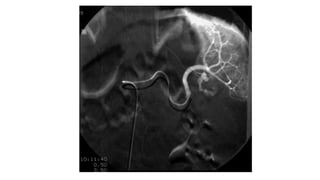

Angiografía

• No se utiliza de primera elección, pero cada día se utiliza mas como

opción terapéutica.

• Casi siempre se realiza después de una TAC, para realizar

angioembolización

Angiografía • No seutiliza de primera elección, pero cada día se utiliza mas como opción terapéutica. • Casi siempre se realiza después de una TAC, para realizar angioembolización